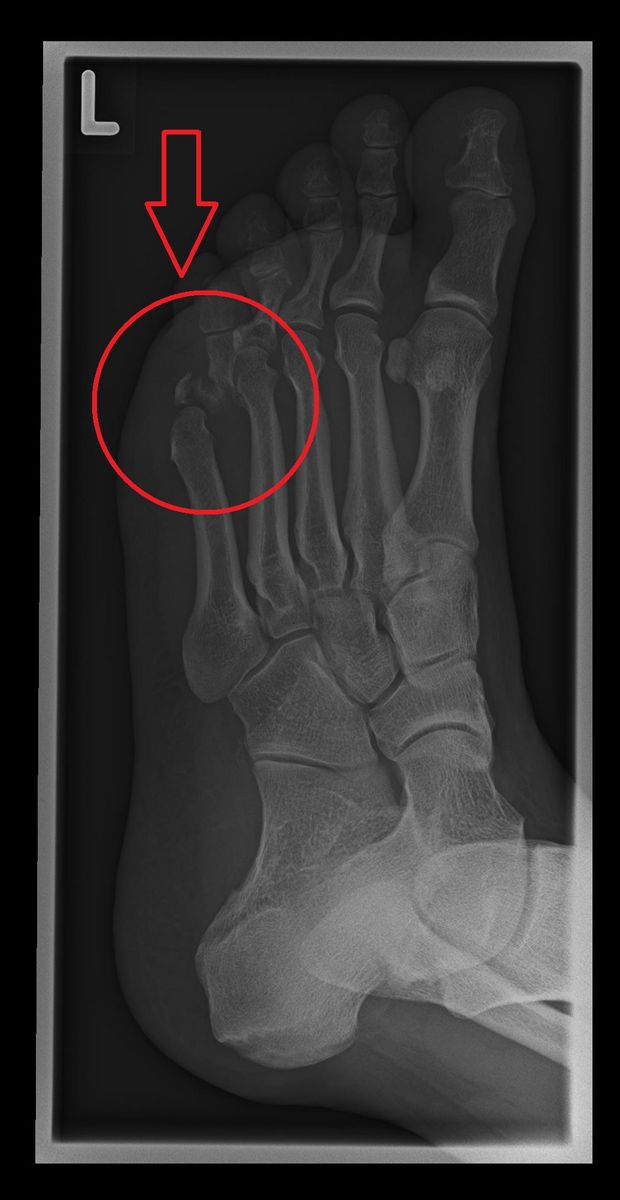

Als Kommandant der burgerlichen Ehrenformation ist man allerlei Gefahren ausgesetzt. Jürg Oehrli, derzeitiger Hauptmann der burgerlichen Ehrengarde musste dies am diesjährigen Zibelemärit anlässlich der Wahl des neuen Oberzibelegrings am eigenen Leib erfahren.